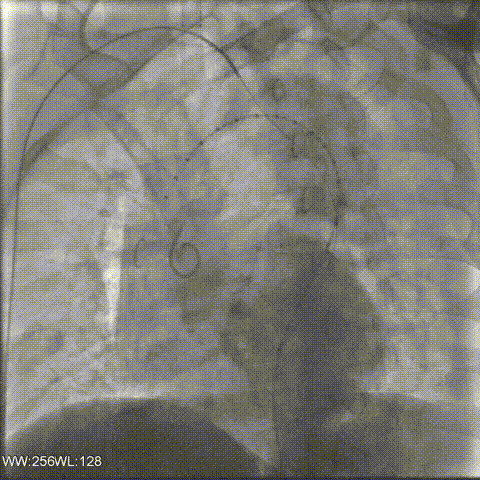

1.经左侧肱动脉和右侧肱动脉切开置管,然后右侧股动脉穿刺,覆膜支架沿左颈总动脉后缘释放,行TEVAR术。之后预备行右侧左锁骨下动脉原位开窗。

2.ARSA造影,尝试右侧针刺开窗。但由于该部位角度不好且路线较长,反复尝试操作后开窗非常困难。为避免发生血管夹层,果断放弃该操作。

3.左侧股动脉穿刺,导丝导管到达主动脉部位,利用Fustar引导,造影定位,在右锁骨下动脉开口膨大处进行顺序穿刺。同时利用右锁骨下动脉导管冒烟定位,顺利穿刺并成功。

右锁骨下动脉置入Viabahn支架和Smart Control支架,左锁骨下动脉同样进行针刺开窗,最终造影情况良好。